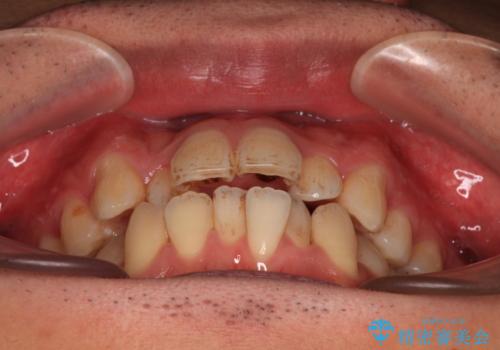

- 口元の突出感が強く、口が閉じにくいことを主訴として来院された患者さんの症例をご紹介します。

前歯部の叢生(デコボコ)も認められ、歯がきれいに並ぶためのスペースが不足している状態でした。

これらの問題を総合的に改善するため、上下左右の第一小臼歯を計4本抜歯し、スペースを確保する治療計画を立てました。